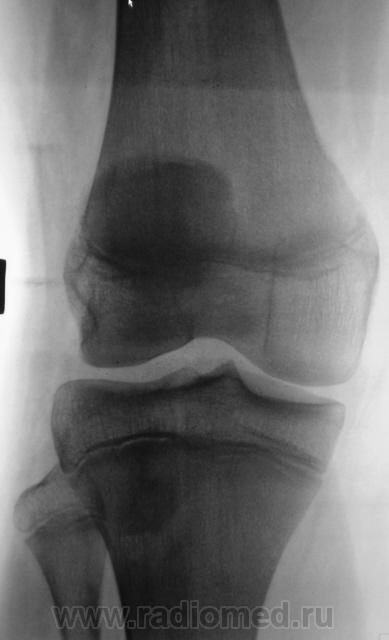

Пациент был направлен на рентгеновское исследования обоих коленных суставов по поводу болеши "Осгут-Шлаттера"

Нет, я был не прав, что утверждал, что на прямой рентгенограмме бугристость не отображается. Мы, на пленке уже вообще не работаем, оказалось, что на "цифре" на прямой отображается и ох, как хорошо.

Да и на пленке отображается )))

Кроме остеохондропатии бугристостей у пациента явная латеропозизия надколенников и бугристостей большеберцовых костей, что свидетельствует о дисплазии мыщелков бедренных костей, вероятнее всего клинически проявляющаяся болями в переднем отделе коленных суставов (под надколенниками).